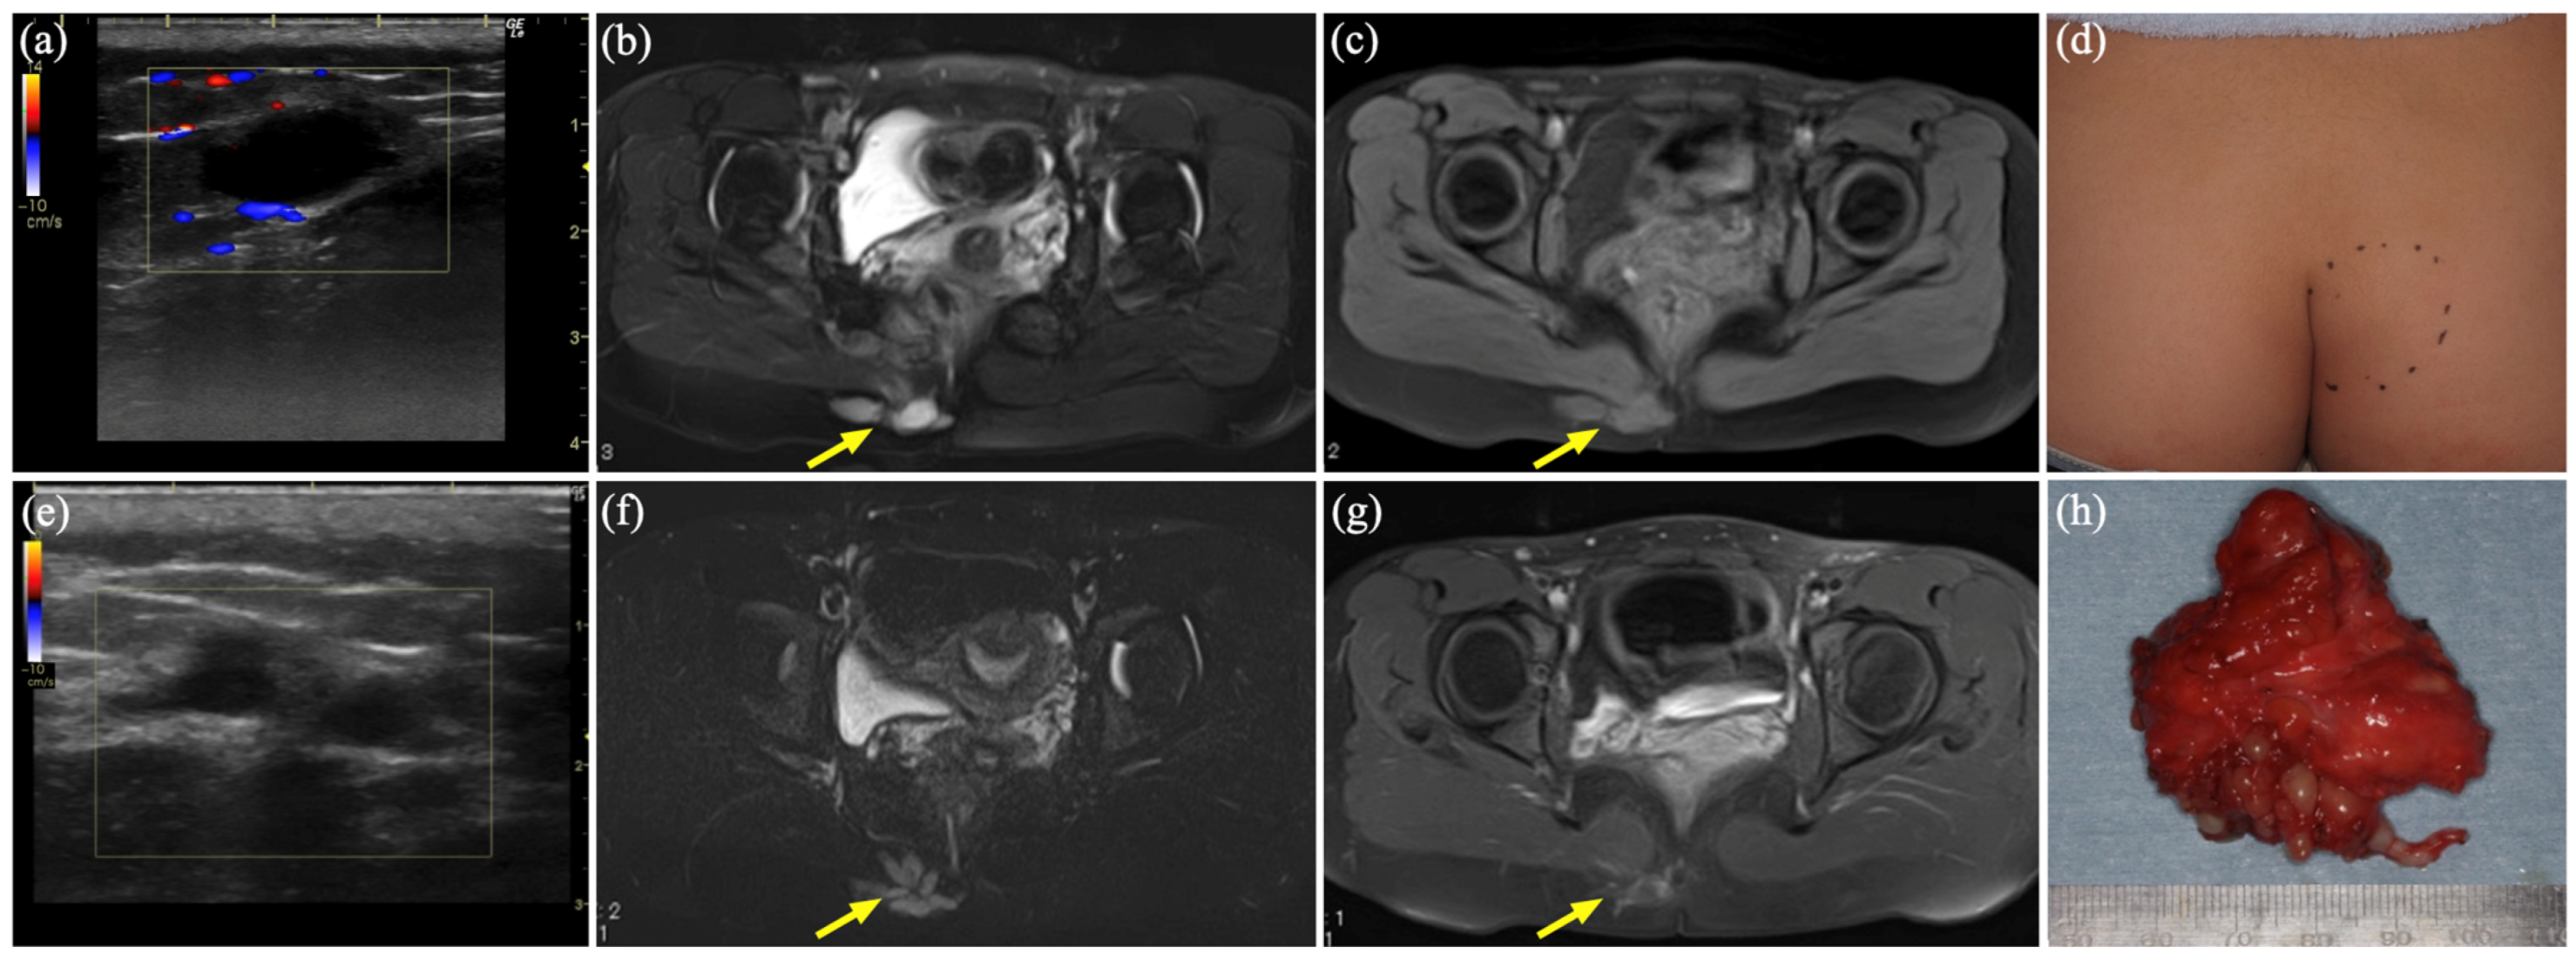

3.4. Case 3

| 2 | 15 | F | Rt buttock | VM | US, MR, CT | Sc, 2 times | Schwannoma | 1186 |